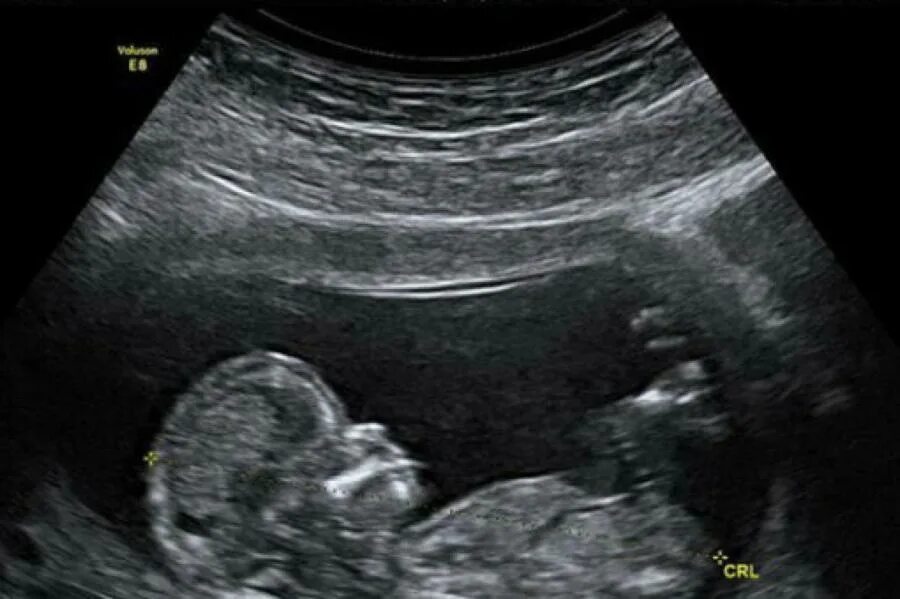

Тянет живот на 12 неделе